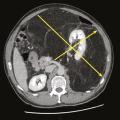

Prise en charge chirurgicale des sarcomes des tissus mous

La chirurgie est la pierre angulaire du traitement des sarcomes des tissus mous (STM). La survie globale des STM dépasse les 70 % à cinq ans ; elle est en amélioration constante d’année en année grâce à une meilleure prise en charge.1,2 La qualité de la chirurgie conditionne la survie globale en cas de sarcome tronculaire…